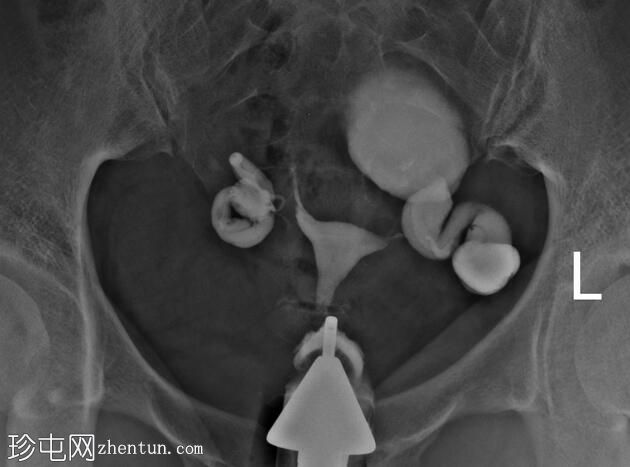

右侧输卵管扩张并充满液体,无腹膜溢出,提示输卵管积水及输卵管阻塞。

左侧输卵管亦扩张并充满液体,伴有造影剂残留及少量溢出,提示输卵管积水及输卵管阻塞。

此外,左侧盆腔内,位于输卵管上内侧,可见大量分隔的造影剂积聚,并伴有盆腔输卵管周围粘连。

子宫输卵管造影结果符合双侧输卵管阻塞和输卵管积水,左侧输卵管周围可见分隔的造影剂渗漏。